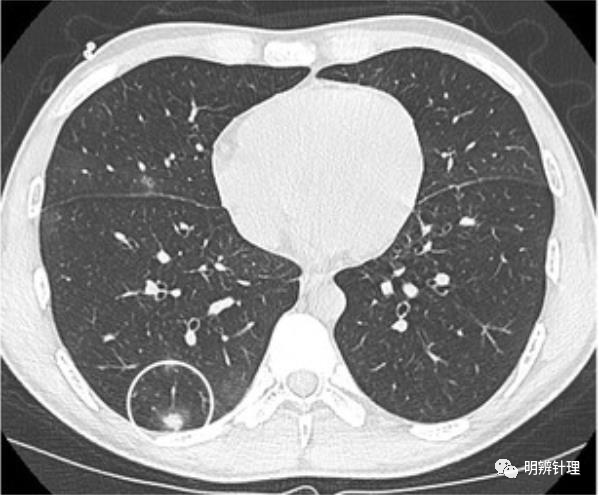

男性,25 岁,骨髓增生异常综合征,免疫功能低下。接受诱导化疗后。肺 CT显示右下叶有一个胸膜下结节。结节以实性为主,周围有磨玻璃晕。右肺小的磨玻璃病灶。

诊断结果:侵袭性曲霉病